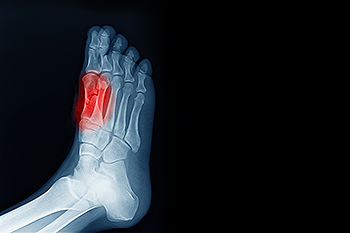

To figure out the cause of foot pain, podiatrists utilize several different methods. This can range from simple visual inspections and sensation tests to X-rays and MRI scans. Prior medical history, family medical history, and any recent physical traumatic events will all be taken into consideration for a proper diagnosis.

In many cases the cause of toe pain is obvious, but in others, a podiatrist may want to use more advanced methods to determine the problem. These can range from simple visual inspections and sensation tests to X-rays and MRI scans. Prior medical history, family medical history, and any recent physical traumatic events will all be taken into consideration for a proper diagnosis.

To diagnose a broken ankle, your podiatrist will first ask you to explain how the injury occurred and what your symptoms are. They will perform a thorough examination, checking for damage to nerves, blood vessels, and other structures around the injury site. They will also test your range of motion. An X-ray will need to be reviewed and, in some cases, an MRI or CT scan may be necessary.